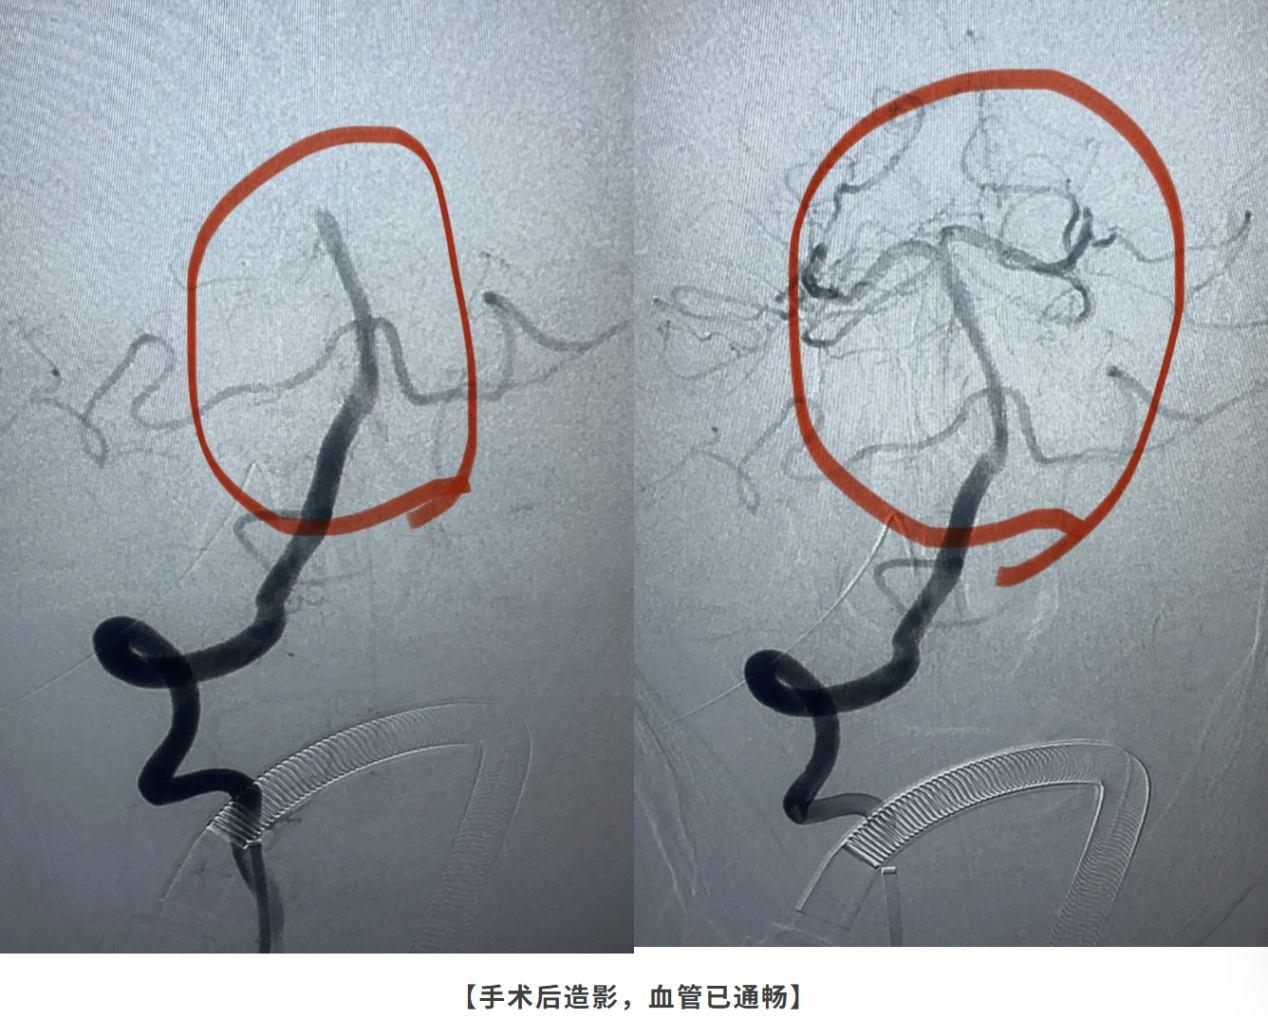

经过一番精细操作,贾颐主任成功取出了一条长约15公分的血栓,彻底疏通了这条“生命主干道”。术后造影显示,原本消失的基底动脉及其分支血管完美显影,血流恢复通畅!

术后第三天老人苏醒

术后第一天的监护尤为煎熬,老人血压、心率一度极不稳定,通过严密监测和精心用药,医护团队始终守护着患者。终于,在术后第三天,奇迹发生了——老人苏醒了过来,能够完成指令动作,脱离了生命危险。贾颐主任表示:“这台手术的成功,不仅挽救了一位老人的生命,更证明了在现代医疗技术下,高龄不再是绝对的手术禁区。只要有百分之一的希望,我们就会付出百分之百的努力。”